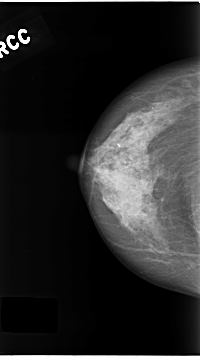

C_0180_1.RIGHT_CC

RIGHT_CC LINES 4680 PIXELS_PER_LINE 2600 BITS_PER_PIXEL 12 RESOLUTION 50 NON_OVERLAY